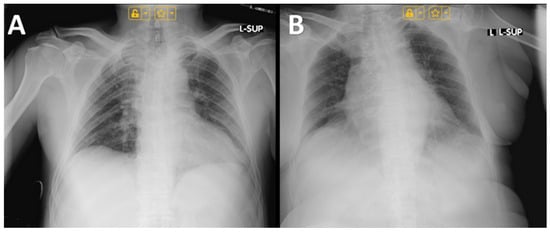

4.3. Imaging Findings